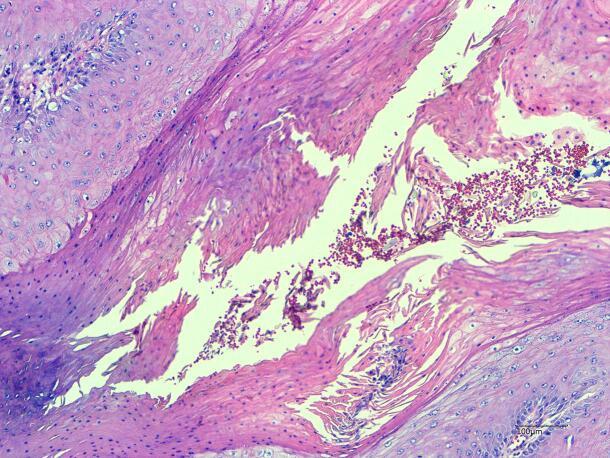

An 82-year-old female presented with a rapidly growing exophytic lesion on the left vulva, measuring 1.5 cm in diameter, accompanied by pruritus. The lesion had been present for two months. The patient underwent vulvar mass excision, and postoperative pathology revealed squamous cell hyperplasia with glassy cytoplasm and no significant cellular atypia. The surgical margins were clear. Three years later, the tumor recurred with disordered growth.

In terms of histological and clinical presentation, keratoacanthoma may overlap with classical well-differentiated squamous cell carcinoma. In rare cases, certain atypical keratoacanthomas may exhibit intravascular and perineural invasion, along with lymph node metastasis. By sharing our treatment experience of a patient with recurrent vulvar keratoacanthoma following surgery, we aim to provide a cautionary perspective for the clinical management of such cases.